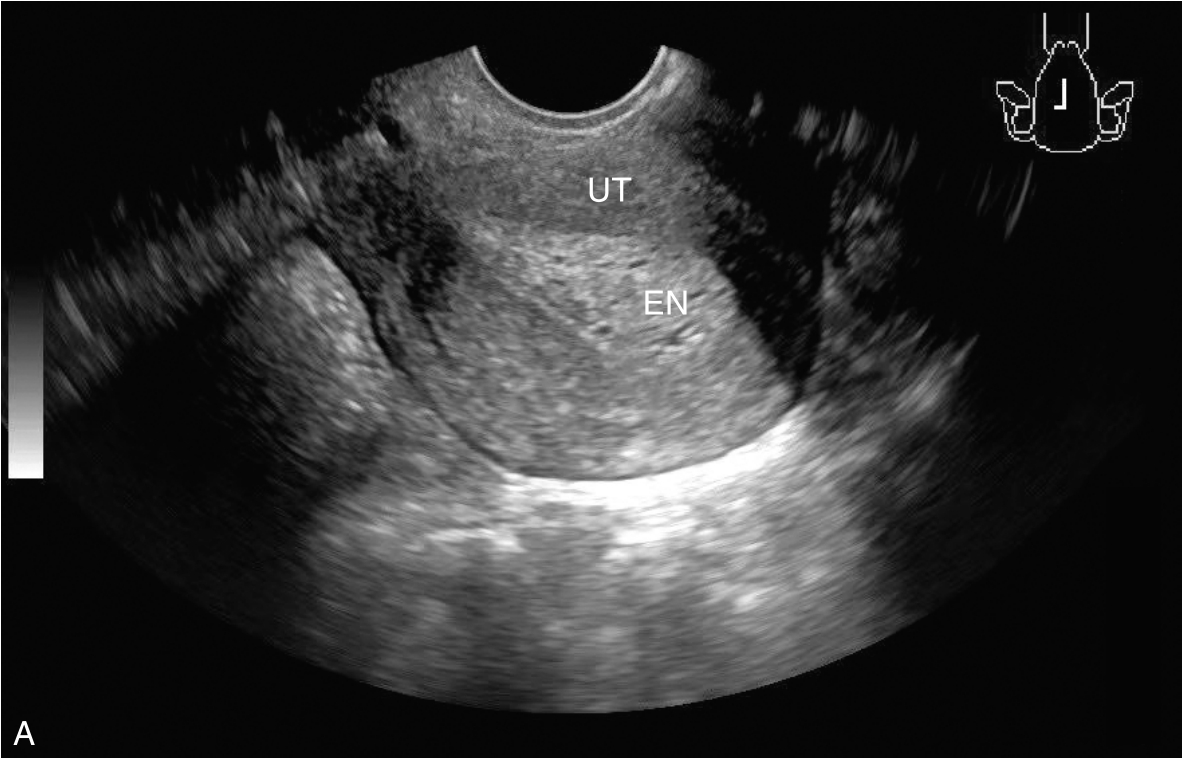

经阴道超声检查见图3-5-1。子宫后位,宫体大小约5.8cm×5.0cm×5.1cm,宫内膜厚约0.75cm(单层),内膜回声不均匀。宫腔未见分离。宫壁回声均匀。内膜内见多个囊性结节,较大者大小约0.5cm,内透声可。CDFI:未见异常血流信号。双侧附件区未见异常回声。盆腹腔未见明显积液。超声检查结果:宫内膜增厚伴回声不均匀。

图3-5-1 常规超声声像图

A.后位子宫的矢状切面(经阴道),子宫内膜增厚,单层厚约0.75cm,内见多个小暗区;B.后位子宫的横断面(经阴道);C.后位子宫的矢状切面(经阴道),彩色多普勒能量图超声检查显示子宫未探及明显血流信号;D.右卵巢;E.左卵巢。UT:子宫;EN:子宫内膜;R-OV:右卵巢;L-OV:左卵巢。